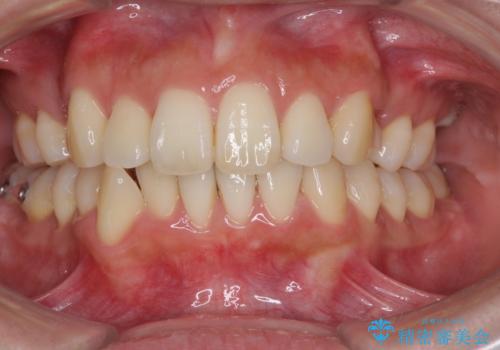

裏側装置で出っ歯の矯正治療

- 出っ歯を目立たない器具で治療したいとのことで来院されました。

上顎の前から4番目の歯を両側抜歯して、上下裏側の装置で前歯を引っ込める計画としました。

裏側からの矯正であったため、表側に比べて少し治療期間を要しました。

目立たずに矯正治療を終えることができ、満足していただけました。